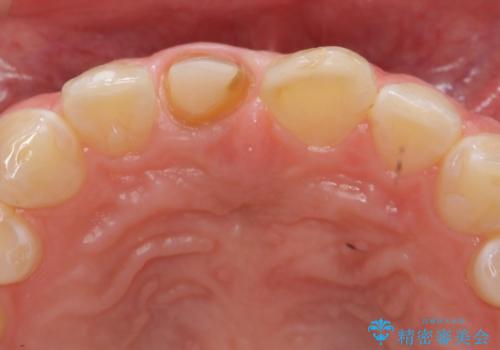

前歯をきれいにしたい ジルコニアクラウンによる審美治療

- 前歯の見た目の改善を求めて来院されました。

ジルコニアクラウンによる審美性の改善を計画します。

失活歯のため捻転を改善し、根管治療は特に希望されなかったのでそのままとしました。

今回失活歯であったため捻転を取り反対側の前歯に揃えて補綴を行うことができました。